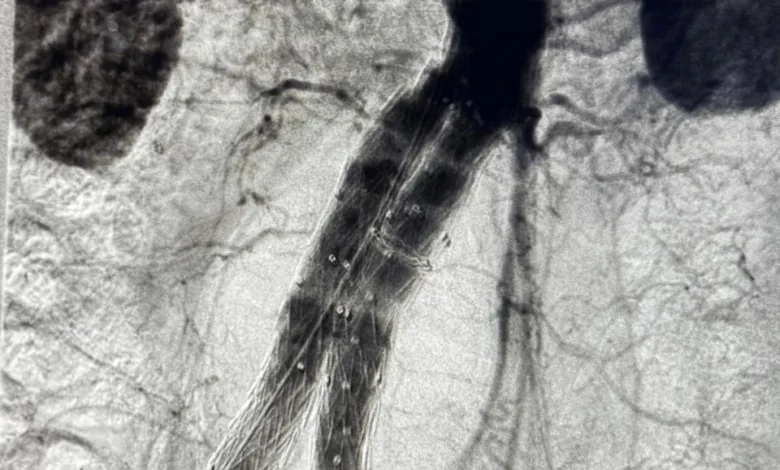

Por primera vez en este centro hospitalario guanacasteco se realizó la cirugía de endoprótesis de aorta abdominal, para mejor comprensión de los usuarios consiste en la colocación de una “malla reforzada” dentro de la aorta para tratar un aneurisma.

“El paciente presentaba un aneurisma de la aorta abdominal, que es una dilatación de esta arteria y que puede llegar a romperse, con una mortalidad altísima. Este es el primer caso que se realiza en nuestro hospital con esta técnica. Anteriormente, estos pacientes debían ser trasladados al hospital México para recibir este procedimiento” detalló el médico.

“La cirugía como tal precisó de una prótesis especial que se coloca endovascularmente, es decir, “por dentro” de los vasos sanguíneos y guiada por rayos X. La duración completa desde que el pacientes es abordado por anestesia y enfermería hasta que terminamos la cirugía fue de poco más de 3 horas” precisó el doctor Rojas Vega.

La endoprótesis funciona como una estructura similar a una sombrilla: es un entramado de malla que da soporte a una tela especial, lo que permite reforzar la pared de la arteria y reducir el riesgo de ruptura.